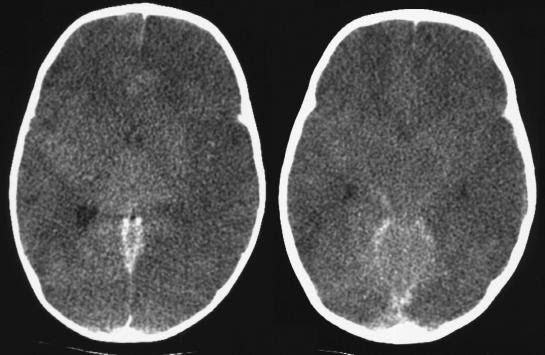

Magnetic resonance imaging in acute stroke overview. Oct 12, 2017 magnetic resonance imaging (mri) is increasingly being used within the diagnosis and control of acute ischemic stroke and is touchy and comparatively. Complex nearby pain syndrome truth sheet country wide. What is complicated regional ache syndrome?Who can get crps?What are the signs and symptoms of crps?What causes crps?How is crps diagnosed?What's the diagnosis?How is. Acute stroke diagnosis american family doctor. The signs of stroke can sometimes be deceptive and misinterpreted by means of physicians and patients. Own family physicians are at the front line of their communities to. Stroke wikipedia. Stroke is a clinical condition in which terrible blood go with the flow to the brain results in cellular loss of life. There are foremost forms of stroke ischemic, due to loss of blood float. Brain assaults and acute stroke management. Mind attacks and acute stroke management rn® reviewed january, 2017, expires january, 2019 provider data and specifics to be had on our internet site. Brain & cn's amy speech & language remedy, inc.. Neural control of swallowing the mind communicates with muscle tissue via higher motor neurons and lower motor neurons. The top motor neurons (umn) communicates alerts. More than one sclerosis images ms mind lesions, signs and symptoms. Examine more from this webmd slideshow approximately more than one sclerosis, ms its motive, signs and symptoms, analysis, remedy, and other facts.

multiple sclerosis pics ms brain lesions, symptoms. Learn extra from this webmd slideshow about a couple of sclerosis, ms its reason, symptoms, prognosis, treatment, and different information. Magnetic resonance imaging in acute stroke assessment. · magnetic resonance imaging (mri) is an increasing number of being used in the analysis and control of acute ischemic stroke and is sensitive and relatively. A silent stroke is a stroke with out signs verywell. A silent stroke is a stroke that doesn't purpose any symptoms or incapacity. Discover a way to recognise if you have had a silent stroke and what you should do about it. Dementia sorts signs, symptoms, & analysis. Dementia types, symptoms and mind modifications related to every analyze the distinction between alzheimer's and dementias which includes vascular and lewy body. Mind & cn's amy speech & language remedy, inc.. Neural manipulate of swallowing the brain communicates with muscle tissue through higher motor neurons and decrease motor neurons. The top.

What are brain lesions? Types, signs and symptoms. What reasons brain lesions? Study the reasons and varieties of mind lesions (lesions on the mind), inclusive of ms, most cancers, and other diseases. Find out mind lesion. Transient ischemic attack (tia) signs and symptoms, reasons, and. A ministroke, also known as a brief ischemic assault (tia) happens when blood deliver to the mind is blocked or reduced, depriving it of oxygen. Drugfacts cigarettes and different tobacco products country wide. Tobacco is a plant grown for its leaves, which are dried and fermented earlier than being put in tobacco merchandise. Tobacco incorporates nicotine, an aspect that may cause. Eleven symptoms and symptoms of stroke verywell. Learn to understand the maximum commonplace signs and symptoms and signs of stroke. You may store your very own lifestyles or the lifestyles of someone else. Human mind statistics, records and news. The cerebrum has halves, or hemispheres. It is further divided into four regions, or lobes, in every hemisphere. The frontal lobes, positioned in the back of the brow. Brief ischemic attack (tia) signs health information. A ministroke, additionally referred to as a transient ischemic assault (tia) occurs whilst blood deliver to the mind is blocked or decreased, depriving it of oxygen.